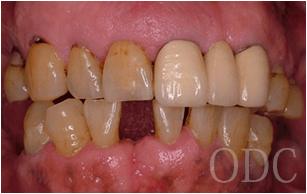

④ 納得のいく口元を創る為に必要な二つの仮歯

オペ当日に1回目の仮歯(ファースト)をインプラントに固定しますが、そのまま最終補綴に移行するクリニックがほとんどです。オペ直後に与える噛み合わせは不十分ですし、審美性や発音等、考慮する事が数多くあります。又、当クリニックでは清掃性を高める為にも、1stの調整を重ねます。最高の最終補綴物を作り上げる為の前段階として、当クリニックでは全ての症例において2回目の仮歯(セカンド)を作製しております。症例によっては、3回目の仮歯(サード)を作制する事もあります。

ファースト

セカンド